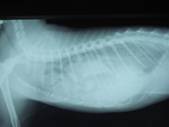

以前から横隔膜ヘルニアと診断を受けていた猫。

急性の呼吸困難を起こし来院。

胸郭内の胃にガスが充満している(胃鼓張)。

救急にて、胃ガス穿刺を行い、状況はいったん安定する。

心陰影はハッキリせず、胸腔内に消化管ガスを認め、

典型的な横隔膜ヘルニアのレントゲンである。